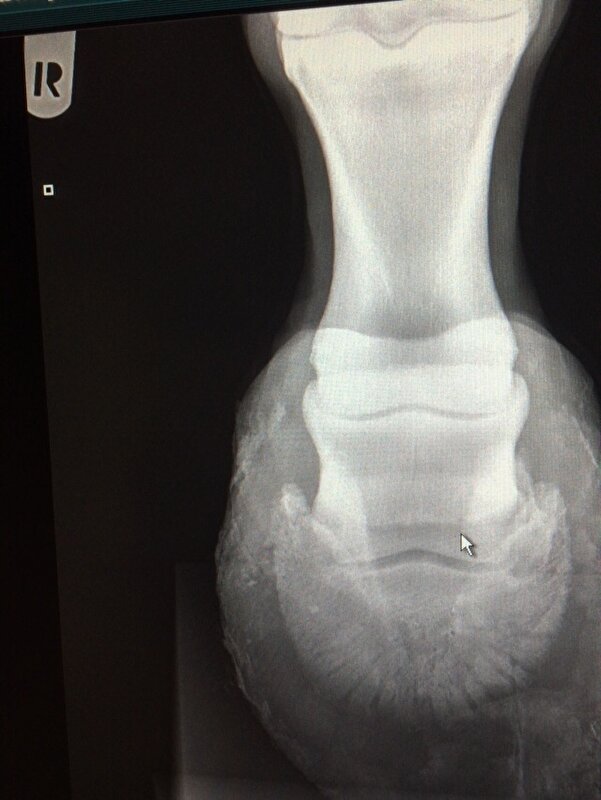

Dus volgens mij werkt het. nuvel schreef:Had gister gebeld maar er was nog niks klaar. Net heb ik de foto's gekregen van beide voorvoeten en het ziet er niet zo goed uit. Beide hoefbenen zijn gekanteld. De ene als je er voor staat is het het linker voorbeen daar komt het hoefbeen bijna door de zool. Als je er voor staat het rechter voorbeen heeft nog een cm voor hij door de zool komt.

Zal straks de rontgenfoto's en foto van het paard hier plaatsen. Ga ze nu eerst naar de kliniek sturen want wil er voor vechten. Dit paard is te sterk en te vrolijk om nu de handdoek in de ring te gooien. Ze staat op dubbele pijnstiller om nu niet te hoeven lijden.